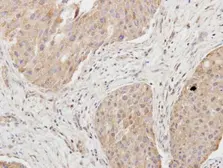

Images